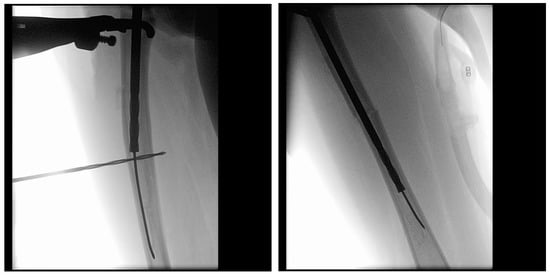

Once the osteotomy is complete, the two bone segments can be reduced to ensure proper alignment (Figure 7a). Reaming can then be performed retrograde into the proximal bone segment through the osteotomy site, and antegrade into the distal bone segment (Figure 7b–d). Under fluoroscopy, external K-wires or SLIM nails are used to measure the required nail length, which is subsequently verified with the actual nail before insertion. Finally, the nail is inserted, positioned centrally in the canal, and advanced until the proximal threads anchor in the epiphysis (Figure 7e). The technique described above and in Figure 7 describes the retrograde approach. In cases with mild deformity (less than 20 degrees in the coronal or sagittal plane) a mini invasive percutaneous osteotomy could be performed, and in such cases, an antegrade approach could be used, in which the insertion of the guide wire, reaming, and insertion of the SLIM nails are all performed through the proximal entry points.

Figure 7.

Intramedullary reaming and SLIM nail insertion. Blue arrows indicate the direction of reaming and nail insertion. (a) Osteotomy is complete. (b) Lateral view of proximal reaming via the osteotomy site. (c) AP view of proximal reaming via the osteotomy site. (d) AP view of distal reaming via the osteotomy site. (e) Insertion of the SLIM nail.